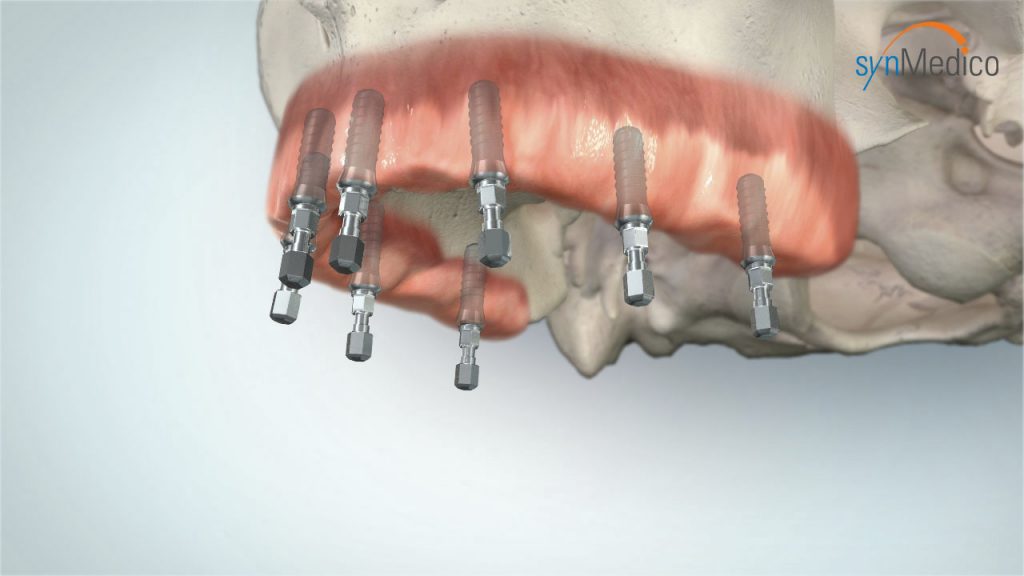

Zahnloser Kiefer

Auch ein zahnloser Kiefer kann mit Implantaten komfortabel versorgt werden. Bereits bestehender Zahnersatz gewinnt auf Implantaten neuen, verbesserten Halt. Das Gesichtsprofil bleibt erhalten, Essen und Lachen ist kein Problem mehr, die Aussprache wird deutlicher. Der Patient kann sich auf einen wirklich funktionierenden Zahnersatz verlassen.